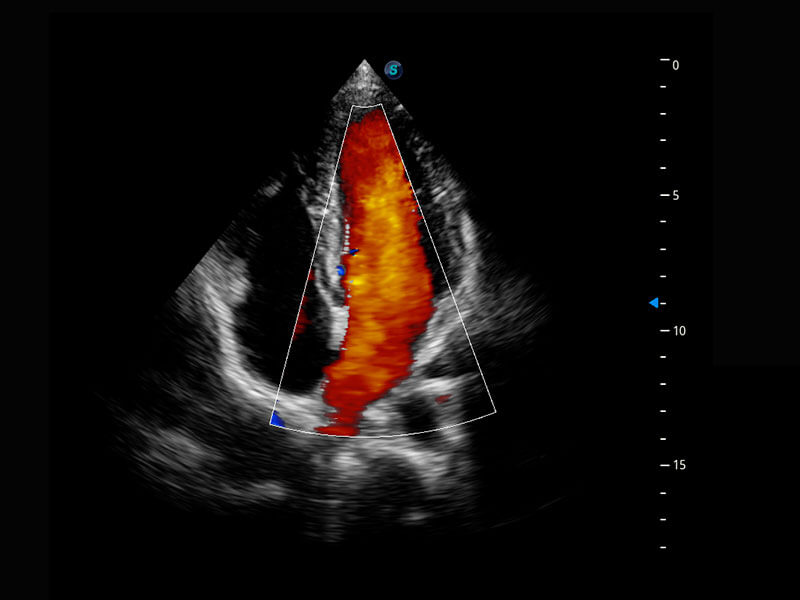

P60搭載一系列胎兒心臟成像技術(shù),實現(xiàn)精細的胎兒心臟評估。

四腔心血流